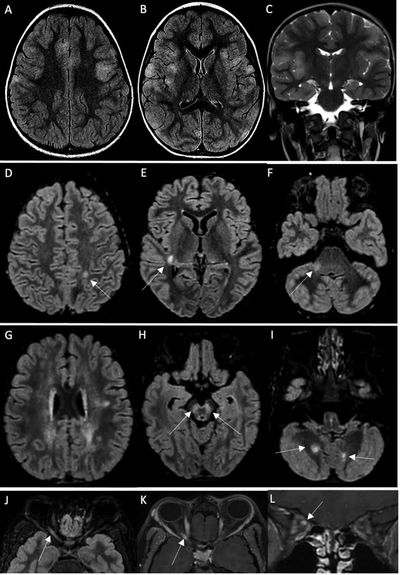

该研究显示,所有患者都有SARS-CoV-2暴露史或核酸检测阳性。在神经系统疾病发作时,8名儿童的新冠病毒核酸检测仍是呈阳性(鼻咽拭子)。58%的患儿(11人)脑脊液异常,74%的儿童(14人)出现MRI异常。

19名患者中有14名MRI异常。4例MRI显示ADEM伴有多灶性脑损伤,1例伴有视神经炎;3例显示胼胝体细胞毒性病变(CLOCC综合征),胼胝体压部扩散受限,T2-FLAIR高信号,2例小脑炎;1例分别显示孤立性视神经炎、孤立性面神经炎和多发性神经炎。19例脊柱MRI中有5例异常:5例显示脊髓炎,其中3例与ADEM相关,1例为孤立性,1例与马尾神经根的对比增强相关。所有脊髓炎病例均显示超过3个椎体受累。